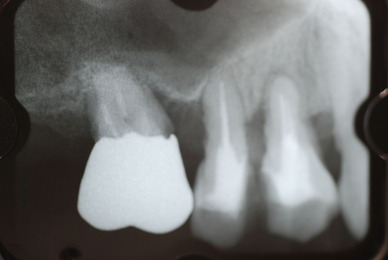

![0a9e48b6-s[1]](https://livedoor.blogimg.jp/netdental/imgs/4/0/40e1507e.jpg)